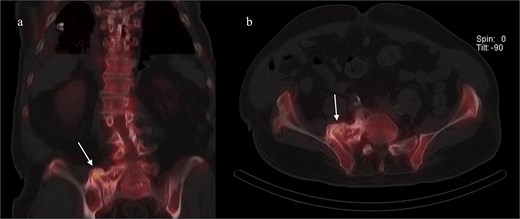

A CT of the pelvis showed significant hyperostosis along the anterior right SI joint and a pseudoarthrosis between the L5 transverse process and the sacral ala that was osteoblastic-appearing in nature (Fig. 1). A SPECT-CT demonstrated increased uptake along the same area, suggestive of inflammatory degenerative changes (Fig. 2).

Coronal CT pelvis (left) and axial (right) demonstrated hyperostosis along the right SI joint suggestive of an osteoblastic lesion between the L5 transverse process and sacral ala (arrows).